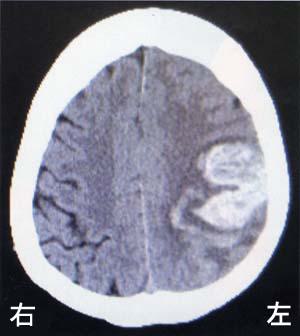

65歳の男性。右利き。突然の意識消失のため救急搬入された。診察時のJCSⅢ-200、血圧210/120 mmHg、脈拍90/分であった。搬送時の頭部CTを示す。意識を回復した際に認められるのはどれか。2つ選べ。

1

左半側空間無視

2

右上肢麻痺

3

左下肢失調

4

相貌失認

5

失語症

65歳の男性。右利き。突然の意識消失のため救急搬入された。診察時のJCSⅢ-200、血圧210/120 mmHg、脈拍90/分であった。搬送時の頭部CTを示す。入院翌日に理学療法が依頼された。JCSⅡ-10、血圧150/100 mmHg、脈拍90/分で、バイタルチェックを行いながら、理学療法を開始することになった。この日に行う訓練で適切なのはどれか。

ギャッジアップ訓練

車椅子座位訓練

健側下肢の筋力訓練

寝返り練習

下肢装具を装着しての立位訓練